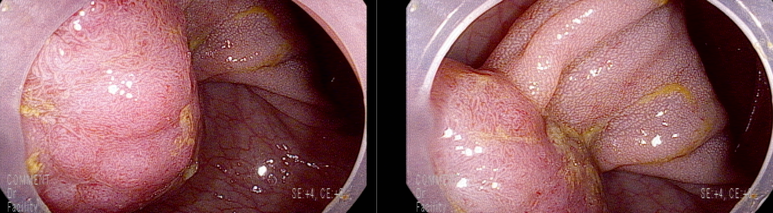

마지막 유경성 거대 용종을 제외하고 점막 소구 패턴(pit pattern)이 불규칙하게 관찰되어(Vi) 고등급의 선종 혹은 점막암을 의심하여 충분히 융기시켜 경계가 확실히 포함되고 한조각으로 완전 절제하기 위해 넓게 절제함

7 mm 크기

7-8 mm 크기